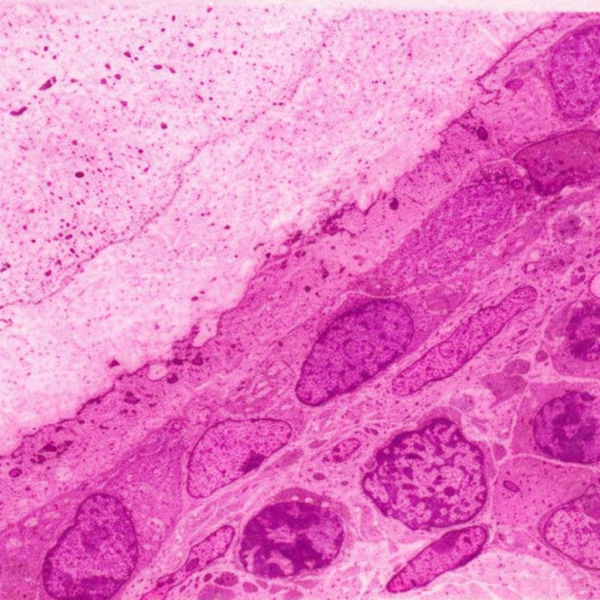

El cartílago en la cabeza y la cara desempeña un papel crucial en el desarrollo y la estructura de estas regiones anatómicas. El cartílago es un tejido conectivo especializado que…